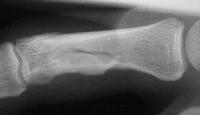

Clinical Example: Proximal phalanx bicondylar oblique volar coronal head fracture

Xrays show a complex intraarticular fracture of the proximal phalanx head. There is a displaced spiral oblique longitudinal fracture with a second oblique coronal split through the articular surface of the radial condyle.

Palmar displacement of a portion of one condyle is visible on the lateral view.